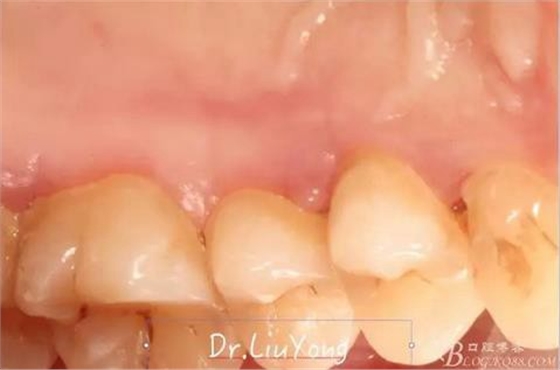

術(shù)后兩周,復(fù)查,A1達(dá)到了完全的根面覆蓋,B1牙齦退縮由原來的3.5mm減少到1mm,B2近中牙齦也得到部分的恢復(fù),同時所有牙齦邊緣都通過手術(shù)增厚。如上圖

A區(qū)結(jié)締組織取瓣區(qū)域的愈合后照片,如上圖